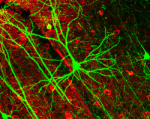

мемристор[White]04.04.2010 23:23 мемристор

мемристор[White]04.04.2010 23:22 мемристор

мемристор[White]04.04.2010 23:21 мемристор

мемристор[White]04.04.2010 23:18 мемристор

мемристор[White]04.04.2010 23:17 мемристор

мемристор[White]04.04.2010 23:12 мемристор

мемристор[White]04.04.2010 23:08 мемристор

мемристор[White]04.04.2010 23:06 мемристор